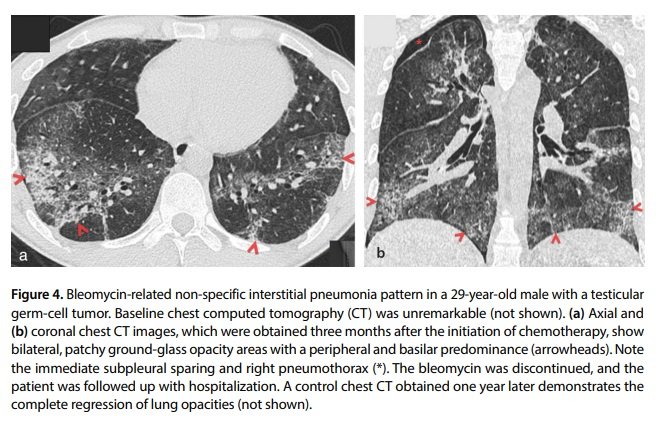

The DAD pattern is characterized by GGOs or dependent consolidation areas on imaging that usually affect the majority of, and sometimes, the entirety of the lung area.

The “crazy paving” pattern characterized by interlobular septal thickening and intralobular lines can often be seen in the DAD pattern. In addition, other patterns, such as OP, can progress to DAD if not treated early.